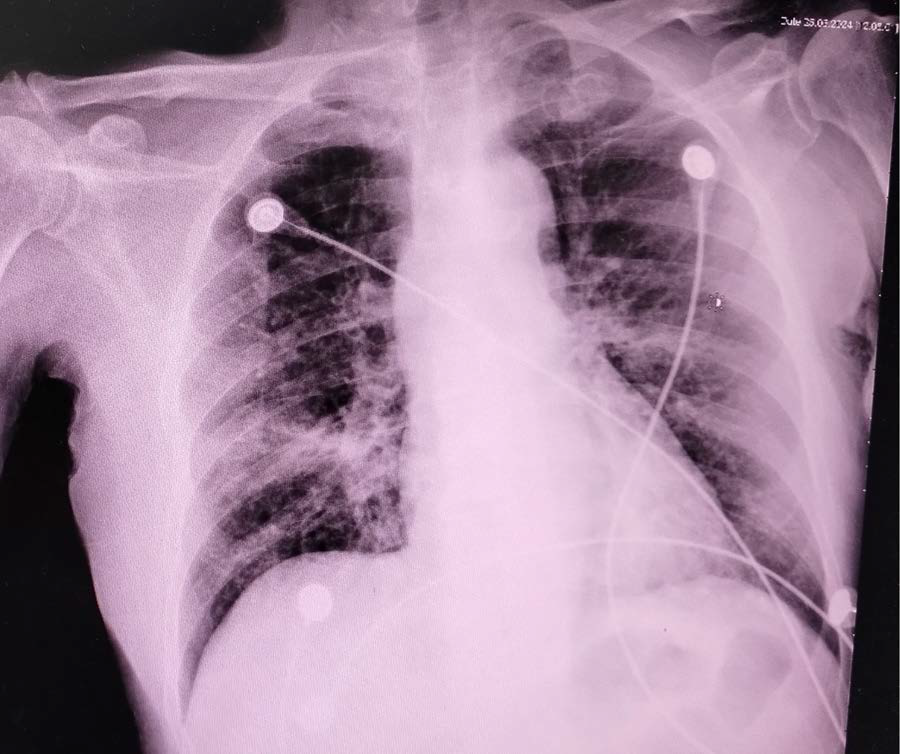

Brass Knuckle Sign: A Collective Appearance of Peribronchial Cuffing

Mohammed Abdullah Juma

1-7